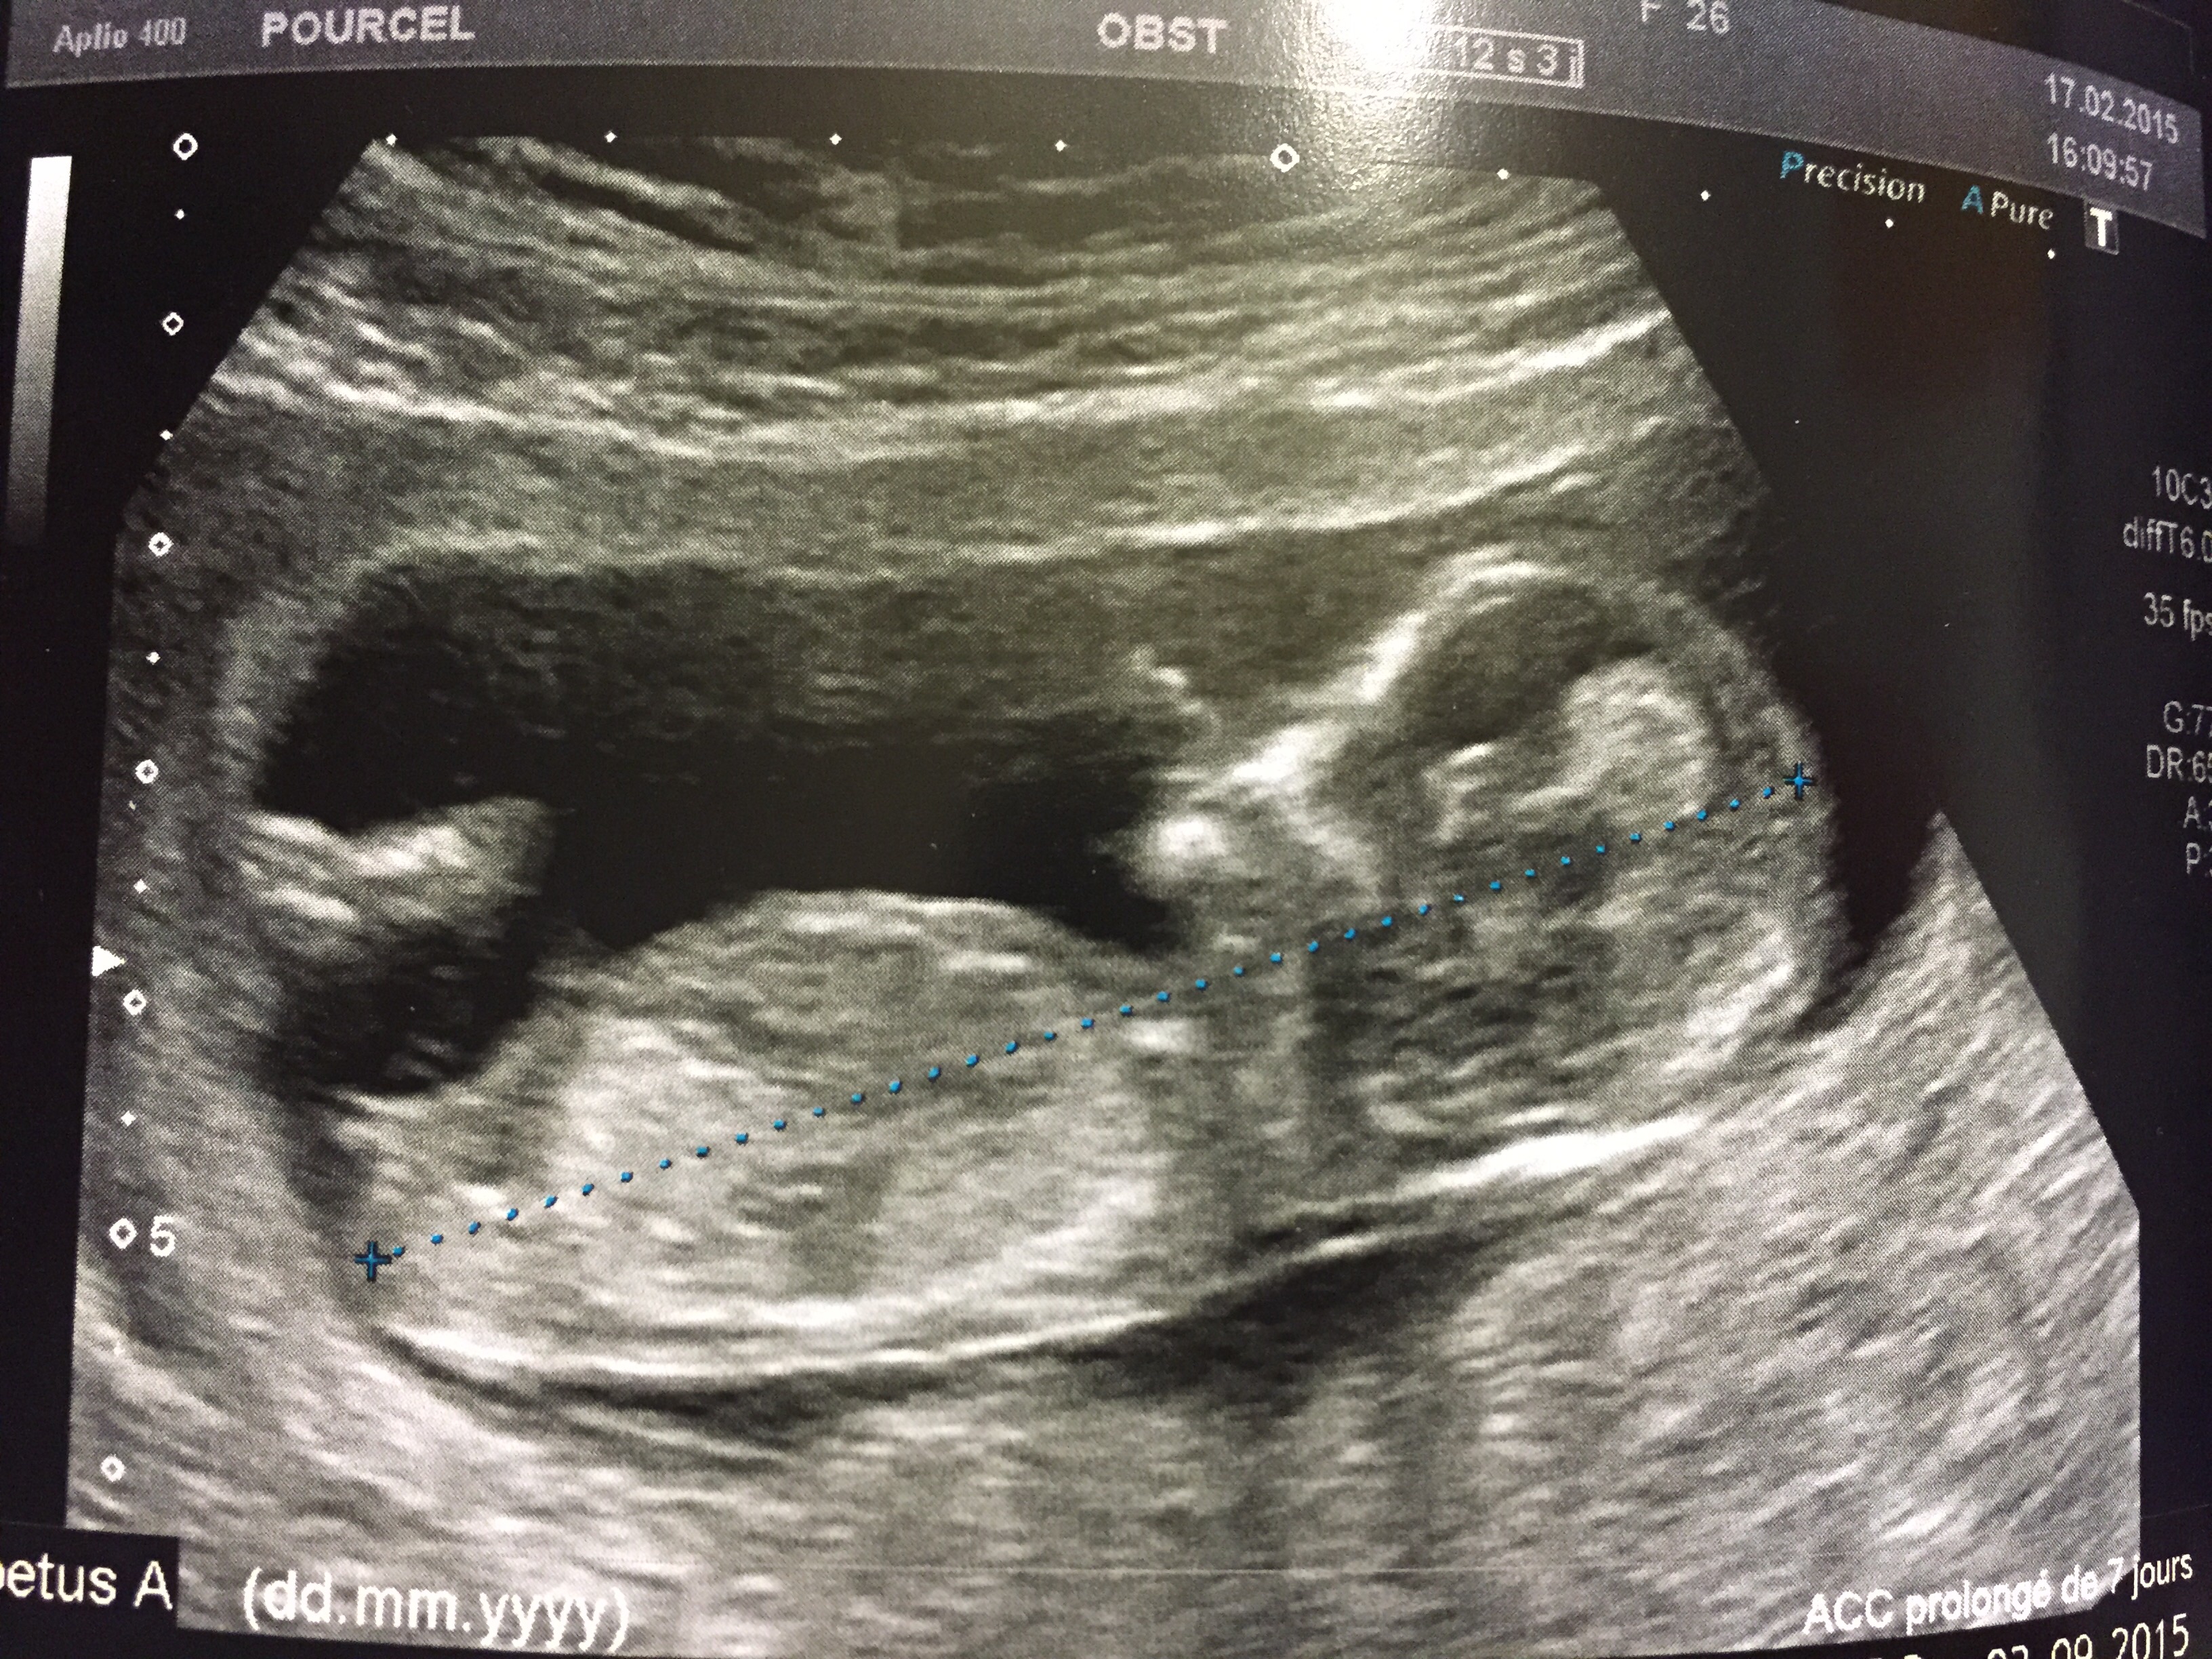

Dernier message posté le à 10h54 Mélodie Nierengarten à 10h43 Alerter Copier le lien Le lien a été copié dans votre pressepapier Bonjour, Voici mon post parmi tant d'autres pour essayer de deviner le sexe de mon bébéLe soir de la première échographie OFFICIELLE celle des 12 semaines d'aménorrhée Nous sommes allés dans un cabinet d'échographie recommandé par madame gynécoSelon les mesures nous étions hier entre 12 sa 3 pour la longueur fémorale (qui est de 803 mm) à 12 sa 6 pour le périmètre crânien (qui est de 229 8mm), et avec 165 bpm pour la fréquence cardiaque !

A voir également Sexe bébé 12 SA Gouter bebe 12 mois Guide Taille bebe 12 sa Guide Miel bebe 12 mois Guide Journée type bébé 12 mois Guide Bebe 12 kg quel age Guide Votre réponseRendezvous avec nos 2 petits bébés d'amour11ème semaine de grossèsseOn la mesure lors du premier trimestre (jusqu'à 14 SA) Elle est de 55 mm en moyenne à 12 SA PC Périmètre Céphalique ou Crânien Il s'agit du tour de tête de votre bébé A la première échographie (12 SA) 68 mm en moyenne A la seconde échographie (22 SA) 199 mm en moyenne A la troisième échographie (32 SA) 297 mm en moyenne

Echo 12 SA 3 jours le 27/07 bébé mesure 63cm et son coeur bat à 153p/m 80% de chances que tu sois une petite princesse On t'aime !30 août 12 To be or not to be PMA Catégories Grossesse Étiquettes Echographie 12 saLa clarté nucale voilà un élément morphologique dont on ignore généralement totalement l'existence tant qu'on a pas été enceinteQu'estce donc ?